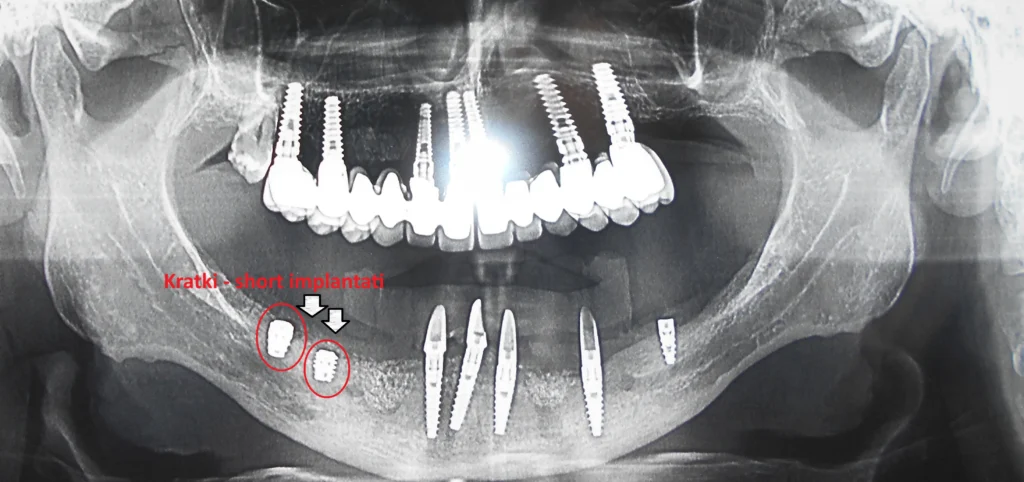

Short (kratki) implantati predstavljaju savremeno rešenje u implantologiji, koji se primenju kod pacijenta koji nemaju dovoljnu količinu kosti u bočnim regijama gornje i naorčito donje vilice, kako bi pružili podršku budućem protetskom radui i doprineli stabinosti i dugotrajnosti protetskog rada.

Za razliku od klasičnih implantata, koji su duži i zahtevaju veću količinu kosti, short implantati su kraći — ali zahvaljujući napretku u dizajnu i materijalima, jednako stabilni i dugotrajni

U situacijama kada u bočnim regijama vilice nema dovoljno koštanog tkiva za ugradnju standardnih implantata, rešenje mogu biti kratki (short) implantati. Ovi implantati predstavljaju savremeno i predvidivo rešenje koje omogućava ugradnju većeg broja implantata u oblastima ograničenog koštanog volumena, bez potrebe za dodatnim augmentacionim zahvatima(nadogradnjom kosti).

Cilj primene kratkih implantata je postizanje ravnomerne raspodele budućih sila žvakanja, čime se obezbeđuje veća stabilnost i dugotrajnost celokupnog protetskog rada kao i ugrađenih implantata. U kombinaciji sa standardnim implantatima, kratki implantati doprinose optimalnom funkcionalnom i estetskom rezultatu.

Short implantati najširu primenu imaju kod pacijenata sa smanjenom visinom kosti u donjoj i gornjoj vilici.

Važno je naglasiti da se kratki implantati nikada ne ugrađuju samostalno, već isključivo kao dopuna standardnim implantatima radi poboljšanja ukupne stabilnosti i biomehaničke ravnoteže sistema. Cena kratkih implantata ista je kao i cena standardnih implantata, jer se u oba slučaja koriste visokokvalitetni materijali i identične hirurške i protetske procedure.